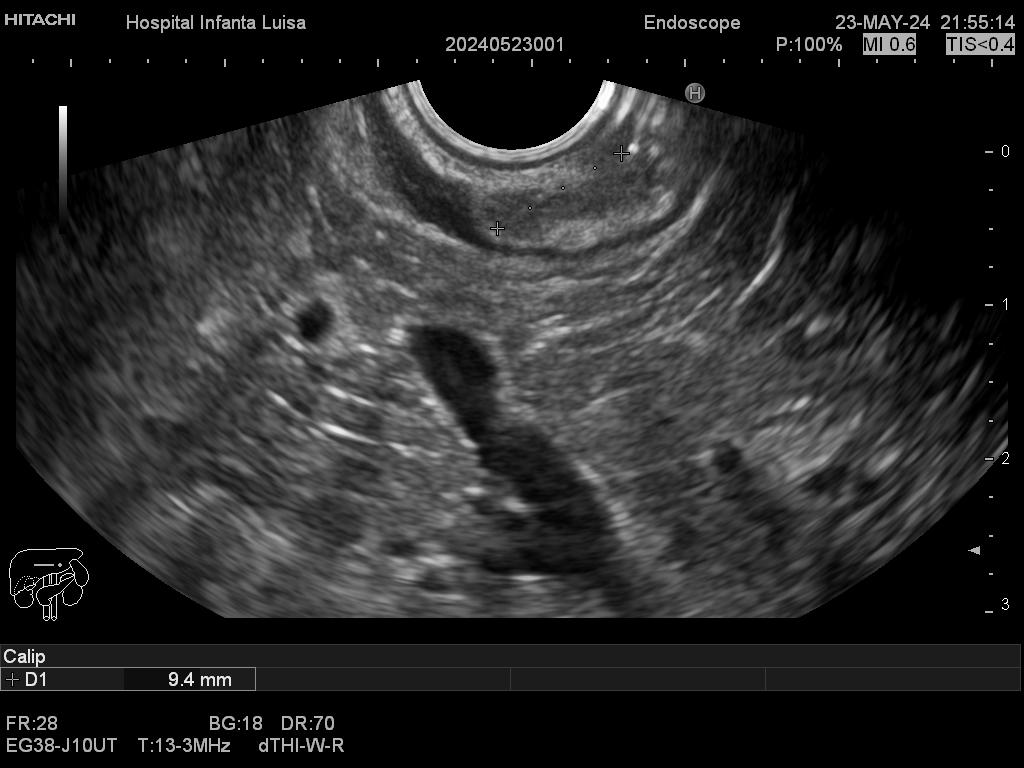

Mediante dicha exploración se explora minuciosamente los tramos mencionados, permitiendo valorar distintas patologías como lesiones propias de la pared de estos órganos (determinado su profundidad y extensión), o lesiones que quedan en órganos anexos, pero por fuera, de ahí la importancia de la visualización ecográfica, como páncreas, mediastino, hígado, diferentes adenopatías o masas indeterminadas previamente, entre otros.

Igualmente, es una técnica básica hoy día en el estudio de todo tipo de lesiones pancreáticas, en la determinación de formaciones subepiteliales esofágicas, gástricas (más frecuentes) o duodenales, o en el estadiaje de patología tumoral a estos niveles. La Ecoendoscopia permite la toma de biopsias a estos niveles, con control endoscópico y ecográfico, siendo una técnica de gran rentabilidad diagnóstica y seguridad.